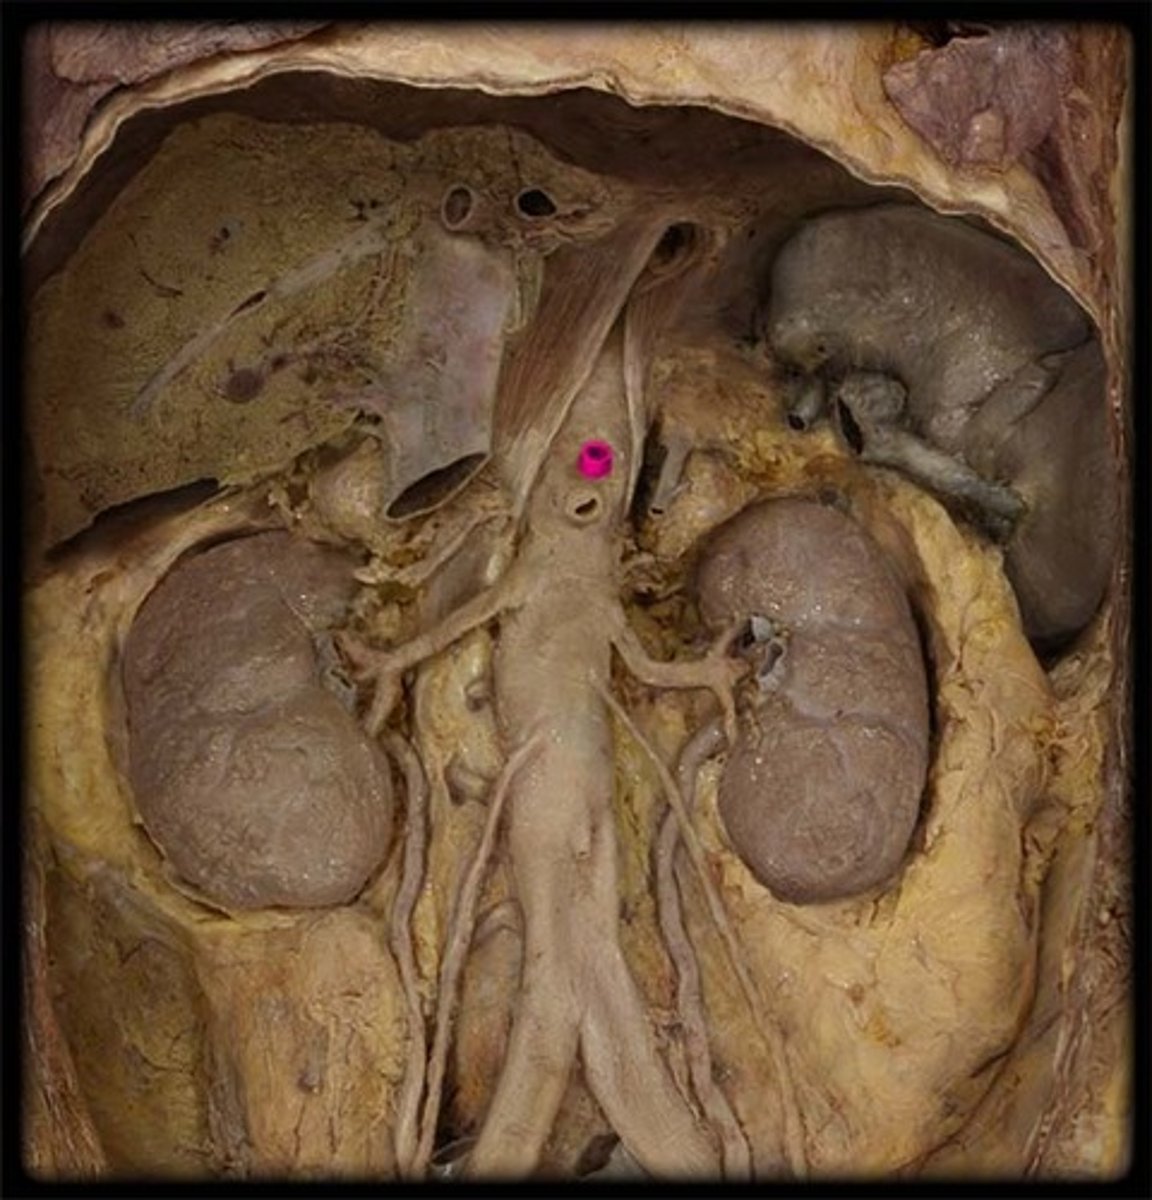

pararenal fat

perirenal fat

hilum (kidney)

left renal vein

inferior vena cava